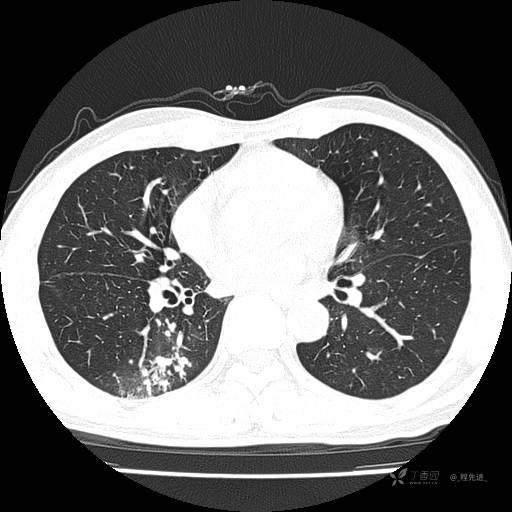

2月特别精彩病例|咳嗽、咳痰20余天,典型病例分享【结果已公布】

患者年龄:51岁

主诉:咳嗽、咳痰20余天

简要病史:20余天前开始出现咳嗽、咳痰症状,阵发性刺激性咳,白色粘痰,不易咳出,无发热,无咯血,无恶心、呕吐等不适,未诊治,咳嗽、咳痰症状持续存在。

体格检查:T:36.3 ℃ P:79 次/分 R:20 次/分 BP:128/64 mmHg,神志清楚,呼吸平稳,双肺呼吸音粗,右下肺闻及细湿性啰音。心率79次/分,节律整齐,各瓣膜听诊区未闻及病理性杂音。腹部未见异常,双下肢无水肿。

辅助检查:我院门诊胸部CT示:如下。心电图:窦性心律;正常心电图。